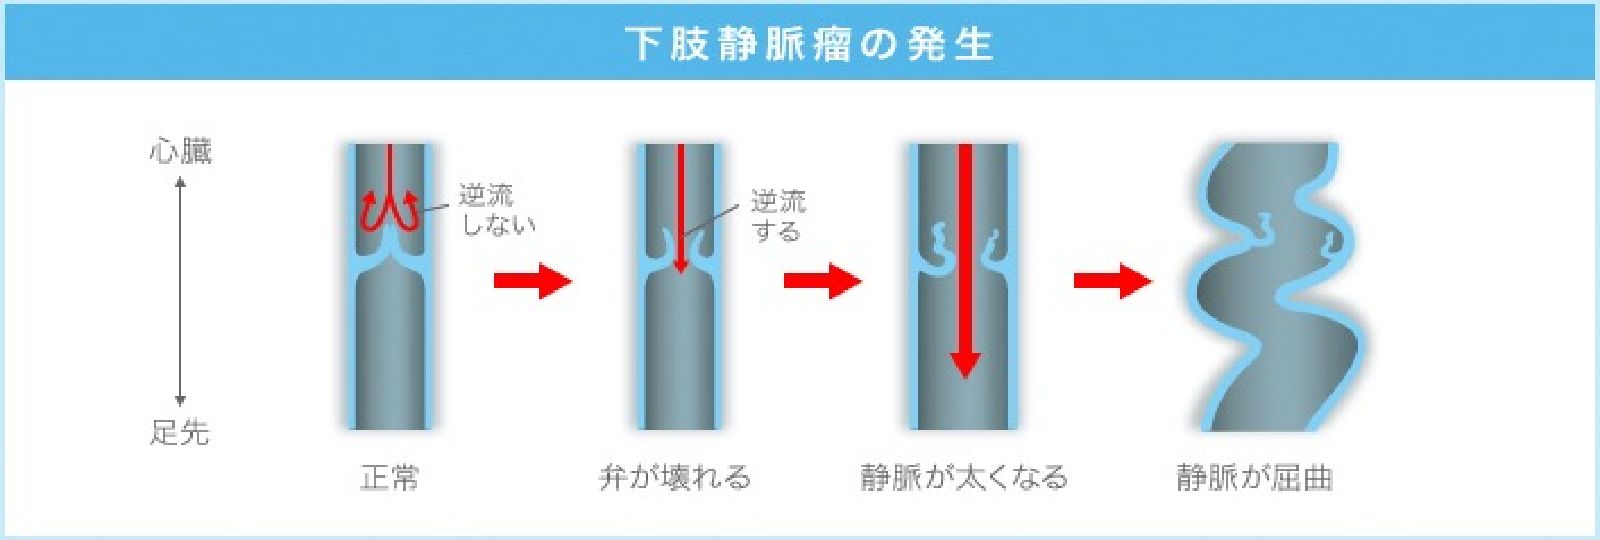

下肢の表在静脈が著明に拡張・屈曲・蛇行した状態で立位で拡張、臥位で縮小するのが特徴です。

静脈弁が壊れる原因は様々ですが、静脈弁が壊れると逆流が生じ、血液が貯留するので太くなり、そして屈曲や瘤化を認めます。